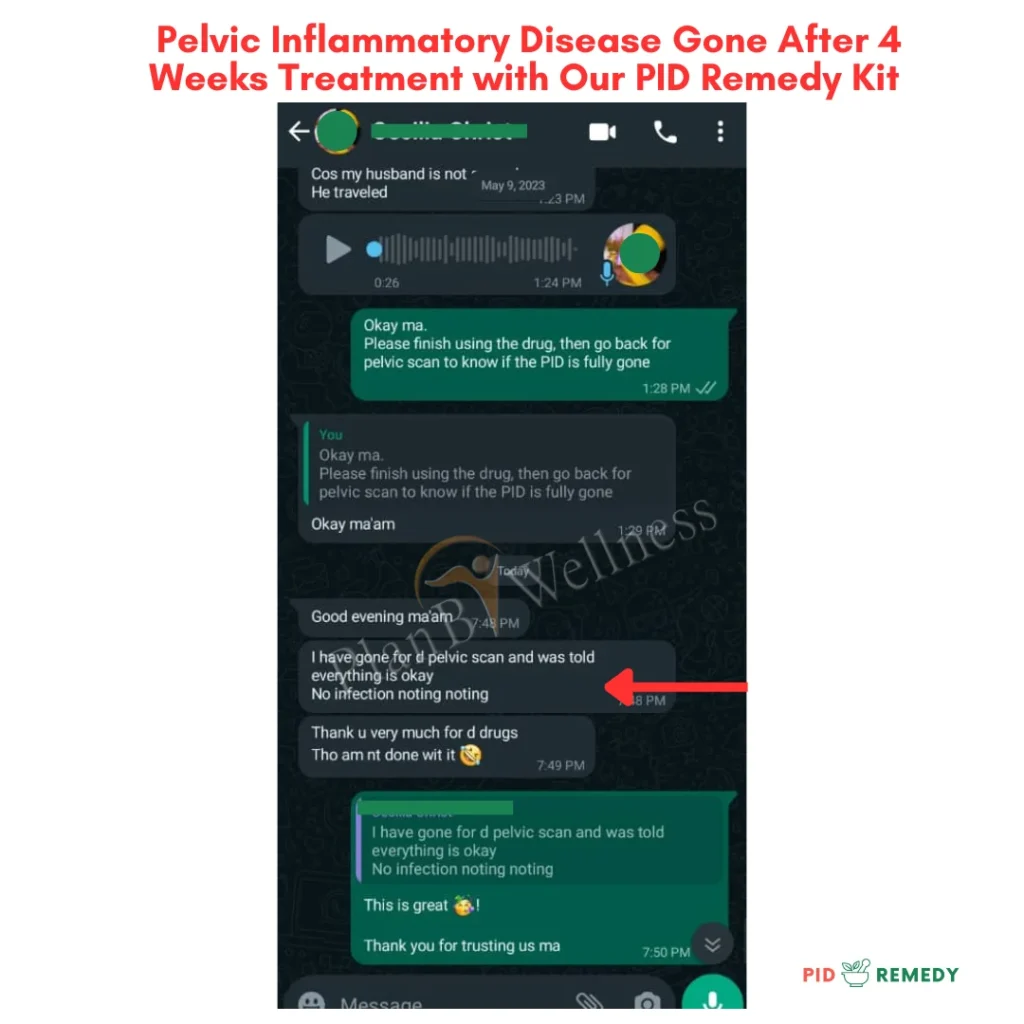

Our Happy Customers Who Love The PID Remedy Kit

Real Reviews From Real People

Our Happy Customers Who Love The PID Remedy Kit

Real Reviews From Real People

More Happy Customers

Real Reviews From Real People